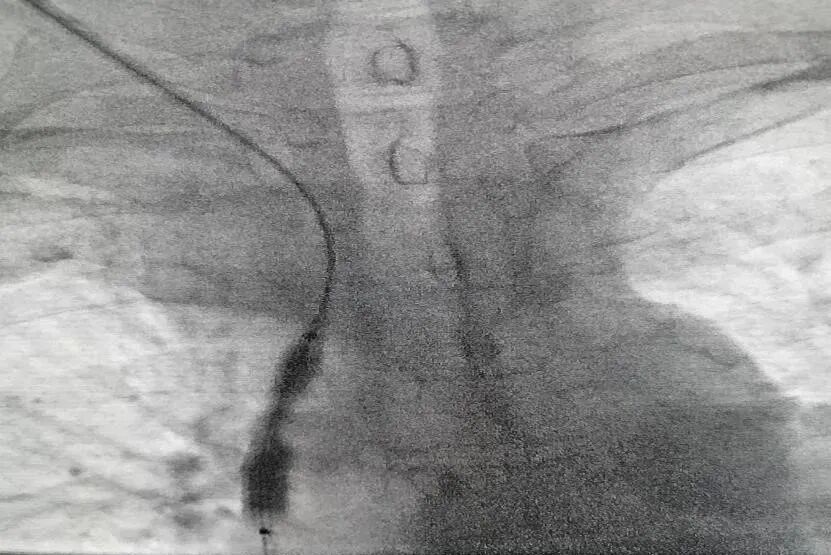

目前该中心能够常规开展肾活检术、腹膜透析置管术、动-静脉内瘘术、肾透析深静脉置管术、血管通路狭窄介入条件下腔内造影+球囊扩张术以及血管通路血栓形成介入条件下取栓术等。血液透析中心现有血液透析机42台,CRRT机2台,长期在该中心接受治疗的维持性血液透析患者已达200余人,腹膜透析中心长期维持性腹膜透析患者150余人。

中心收治肾内专业各种常见病、多发病及疑难危重症,如:原发及继发性肾小球疾病、肾小管-间质疾病、肾血管疾病、遗传性肾脏病、急(慢)性肾衰竭等疾病,独立开展超声引导下肾穿刺活检术,超声引导下透析长期管置入术,动静脉人工成形术(常规内瘘成形术,高位内瘘成形术,动静脉内瘘转位成形术),动静脉人工血管转流术,血管通路并发症开放性手术(动静脉内瘘动脉瘤切除+缩窄术,动静脉内瘘切开取栓术,头静脉弓狭窄切除+吻合术),腹膜透析置管术,腹腔镜下腹膜透析置管术,腹腔镜下腹膜透析置管网膜包裹松解术,血管通路狭窄介入条件下腔内造影+球囊扩张术,血管通路血栓形成介入条件下取栓术,血管通路闭塞介入条件下再通术,介入条件下中心静脉透析导管置入术,介入条件下中心静脉造影+球囊扩张术等肾脏病诊治和血液净化血管通路建立和维护手术,同时开展ANCA综合治疗,急进性肾小球肾炎综合治疗,溶血性尿毒症综合治疗等疑难危重病人特殊治疗技术。